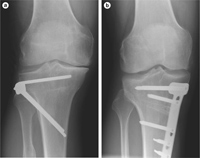

ΕΠΑΝΟΡΘΩΤΙΚΗ ΧΕΙΡΟΥΡΓΙΚΗ - ΓΟΝΑΤΟ

Η θεραπεία εξαρτάται από το στάδιο της νόσου και από την ηλικία του ασθενούς. Στα αρχικά στάδια μπορεί να περιλαμβάνεται ξεκούραση βάδιση με πατερίτσες, αντιφλεγμονώδη και παυσίπονα φάρμακα. Δυστυχώς με την πάροδο των ετών η νόσος και η φθορά επιδεινώνονται με αποτέλεσμα τα συντηρητικά μέτρα να καθίστανται ανεπαρκή. Στις περιπτώσεις αυτές η θεραπεία είναι χειρουργική. Στους ασθενείς άνω των 60 ετών η χειρουργική θεραπεία είναι η ολική Αρθροπλαστική γόνατος. Πρόκειται για χειρουργική επέμβαση αντικατάστασης αρθριτικών επιφανειών μηρού και κνήμης με ειδική πρόθεση που μιμείται τη λειτουργία του φυσιολογικού.

Η επέμβαση αυτή συνοδεύεται από πολύ υψηλό ποσοστό επιτυχίας και προσφέρει γρήγορη κινητοποίηση του ασθενή από τις πρώτες μετεγχειρητικές μέρες. Σε νεώτερους ασθενείς και εφόσον υπάρχουν οι σωστές ενδείξεις μια επέμβαση που αποτελεί την καταλληλότερη επιλογή είναι η υψηλή οστεοτομία της κνήμης. Η επέμβαση αυτή έχει σκοπό να αποφορτίσει το διαμέρισμα που παρουσιάζει την μεγαλύτερη φθορά ώστε να ανακουφισθεί ο ασθενής από τα συμπτώματα.